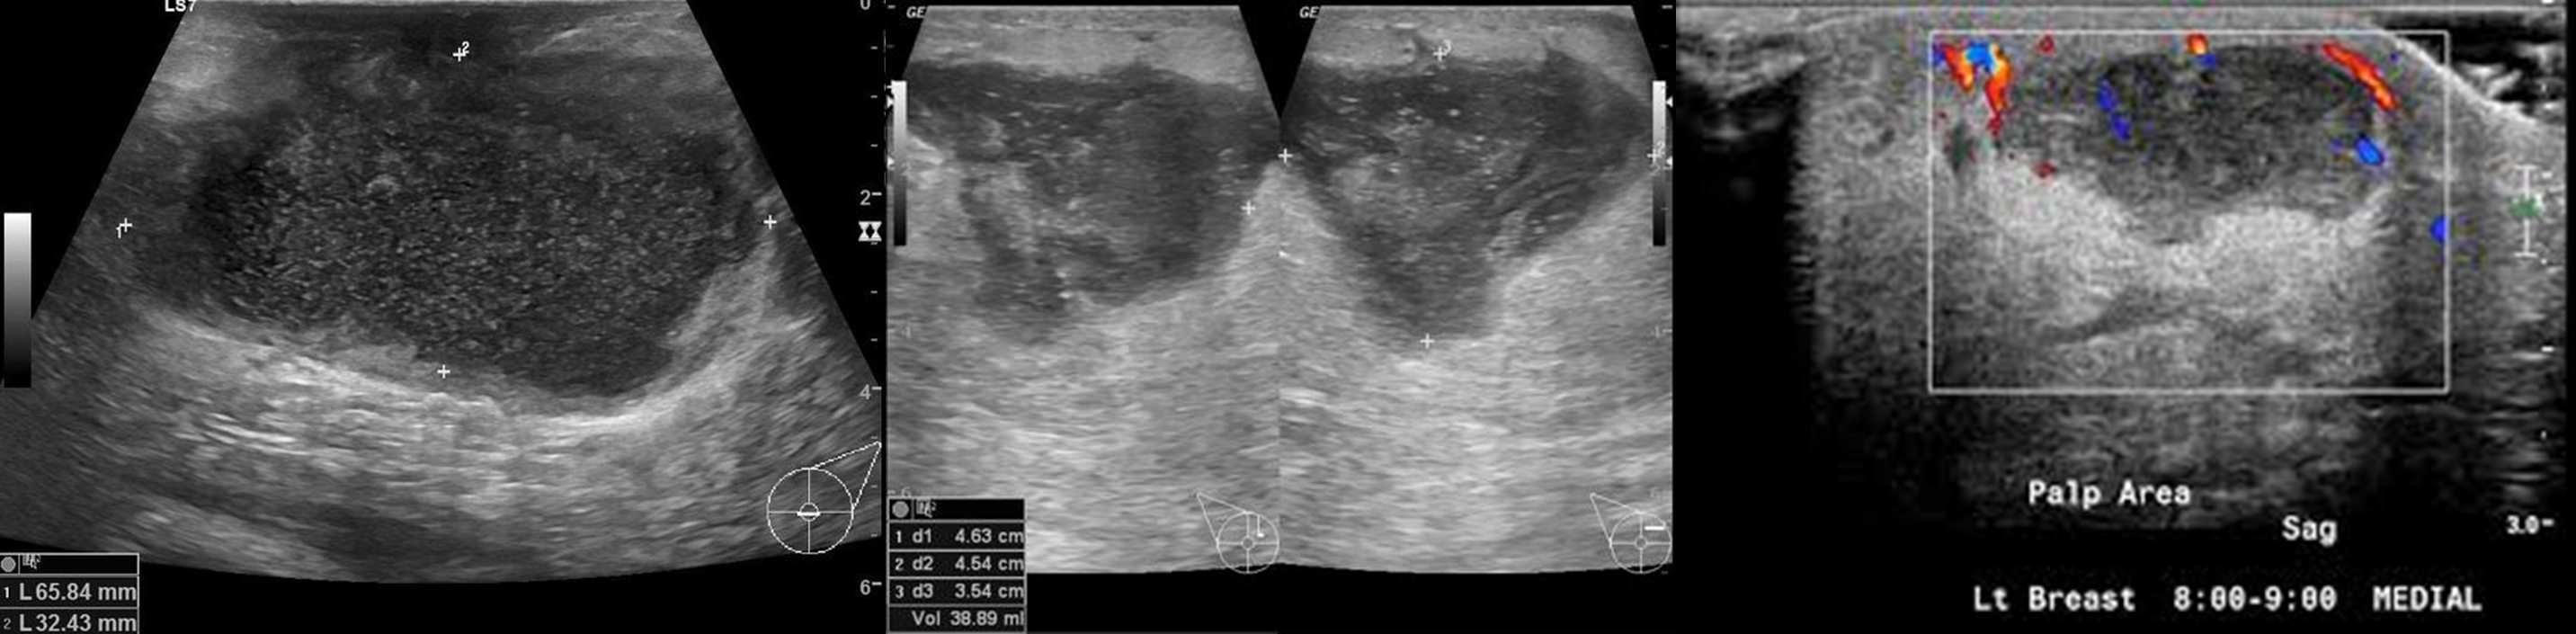

• 초음파 소견

• hypoechoic mass, internal septation/debris

• wall thickening, skin thickening

• increased doppler flow in the walls & surrounding tissue (내부는 vascularity 없음)